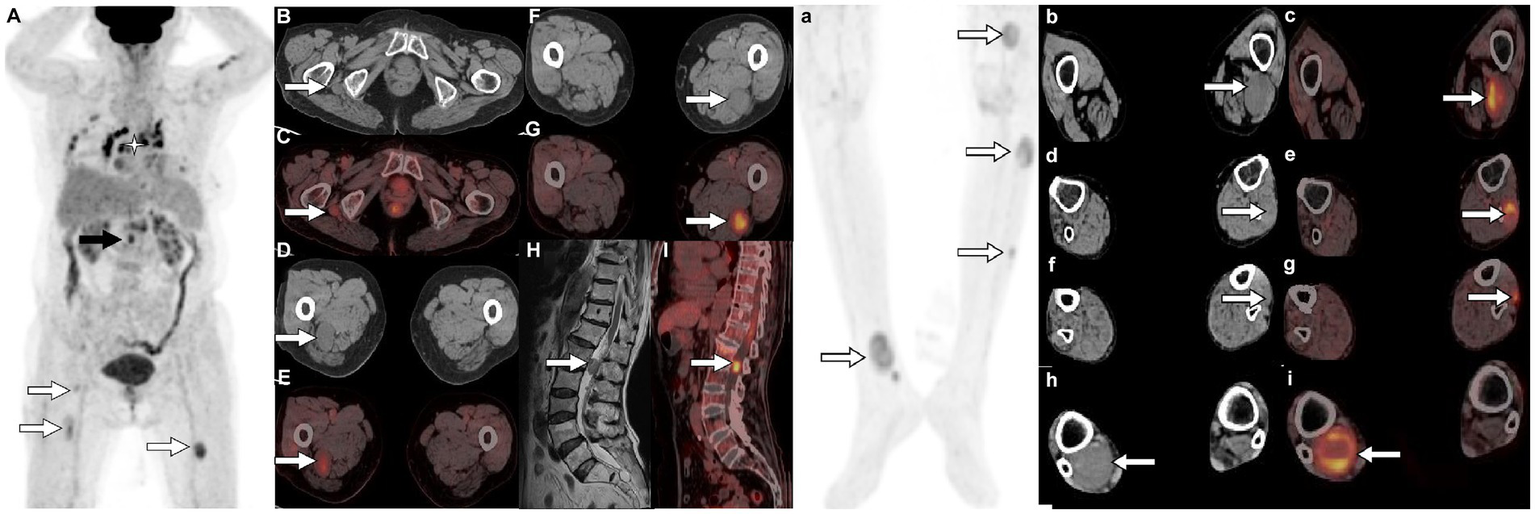

Figure 2

18F-FDG PET/CT [(A,a) Maximum intensity projection (MIP)] was subsequently performed to further evaluate the patient’s whole-body condition and revealed multiple nodules of hypermetabolic uptake in the lumbar spinal canal (black arrow) and lower limbs (white arrows). Besides, multiple high metabolic nonspecific lymph node uptakes were observed in the mediastinum (asterisk arrow). Tomographic images show multiple soft tissue density nodules with high FDG uptake on the lateral side of the right ischial tuberosity [(B) CT; (C) PET/CT fusion; arrows], upper thigh [(D) CT; (E) PET/CT fusion; arrows], middle [(F) CT; (G) PET/CT fusion; arrows] and lower left thigh [(b) CT; (c) PET/CT fusion; arrows], upper [(d) CT; (e) PET/CT fusion; arrows] and middle leg [(f) CT; (g) PET/CT fusion; arrows; SUVmax 7.5], and lower right leg [(h) CT; (i) PET/CT fusion; arrows]. In addition, isomuscular signal on T1WI (H, arrow) and high metabolic uptake nodule on PET/CT (I, arrow) were also observed in the posterior spinal canal of the first lumbar spine.

The presentation of schwannomatosis frequently manifests as imaging features characteristic of schwannoma. The CT scan typically reveals a round or oval density with a well-defined boundary and a low-density shadow in some areas with cystic degeneration (27). The MRI findings of this condition are characterized by equal or low signals on T1WI and slightly high or high signals on T2WI (28, 29). Multifocal schwannoma in 18F-FDG PET/CT is rarely described in the literature and occurs more frequently in the head and neck, spinal canal, and upper limb (30–33). The cases we reported were located in the pelvis, lower limb, and lumbar spinal canal, which are rarely reported in the literature. These tumors have a certain correlation between 18F-FDG PET/CT and contrast-enhanced T1WI. The Antoni A region rich in tumor cells showed significant enhancement on contrast-enhanced T1WI, and the corresponding region presented increased 18F-FDG uptake on PET/CT. While Antoni B areas rich in mucoid substances show low enhancement on contrast-enhanced T1WI, accompanied by mildly increased 18F-FDG uptake. The comprehension of these findings is crucial for the exploration and elucidation of multifocal enhancements in 18F-FDG activity within schwannomas. The 18F-FDG uptake of schwannomas varies greatly with the components of the tumor. Moreover, our case showed that 18F-FDG PET/CT can also accurately locate each tumor in schwannomatosis, and more hidden lesions can be found. In addition, the diagnosis of schwannomatosis should exclude the presence of vestibular schwannoma, requiring an MRI examination for confirmation.